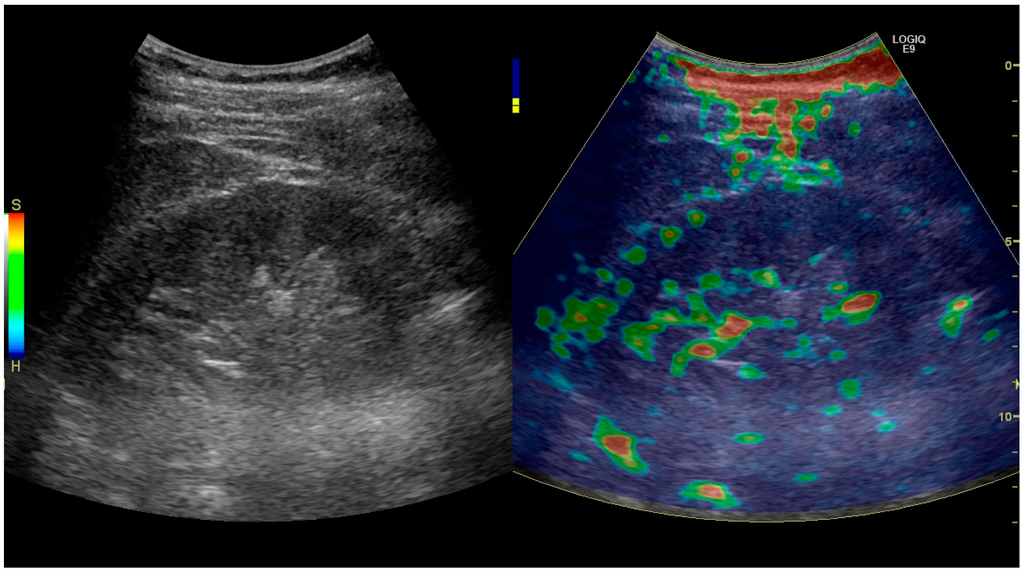

Elastography is a US method to visualize the elasticity of tissue. Preliminary reports on US elastography used on transplanted kidneys to evaluate cortical fibrosis have been published showing promising results (Figure 32) [40].

Figure 32. Strain elastography of a normal kidney. Red depicts soft areas, and blue depicts hard areas relative to the entire elastography image. Note that the medulla is softer than the cortex. A color bar is shown to the left of the image, where ‘S’ and ‘H’ denote soft and hard tissue, respectively.